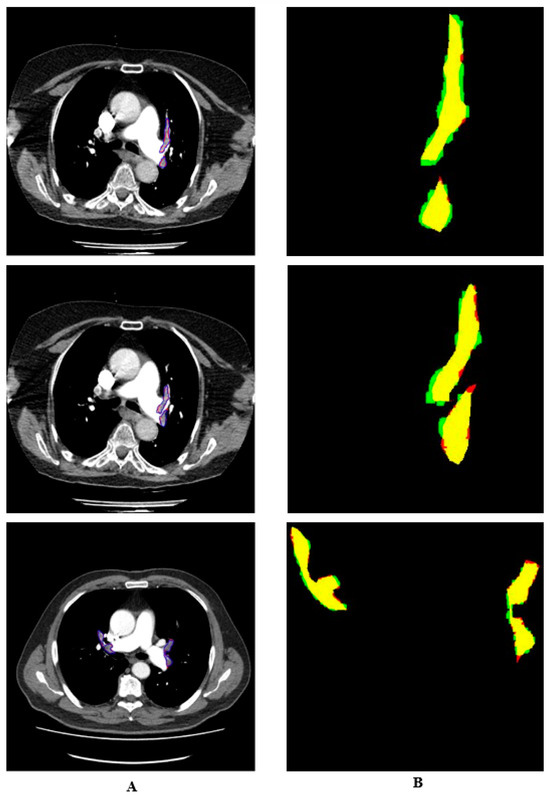

2.2. Pre-Processing